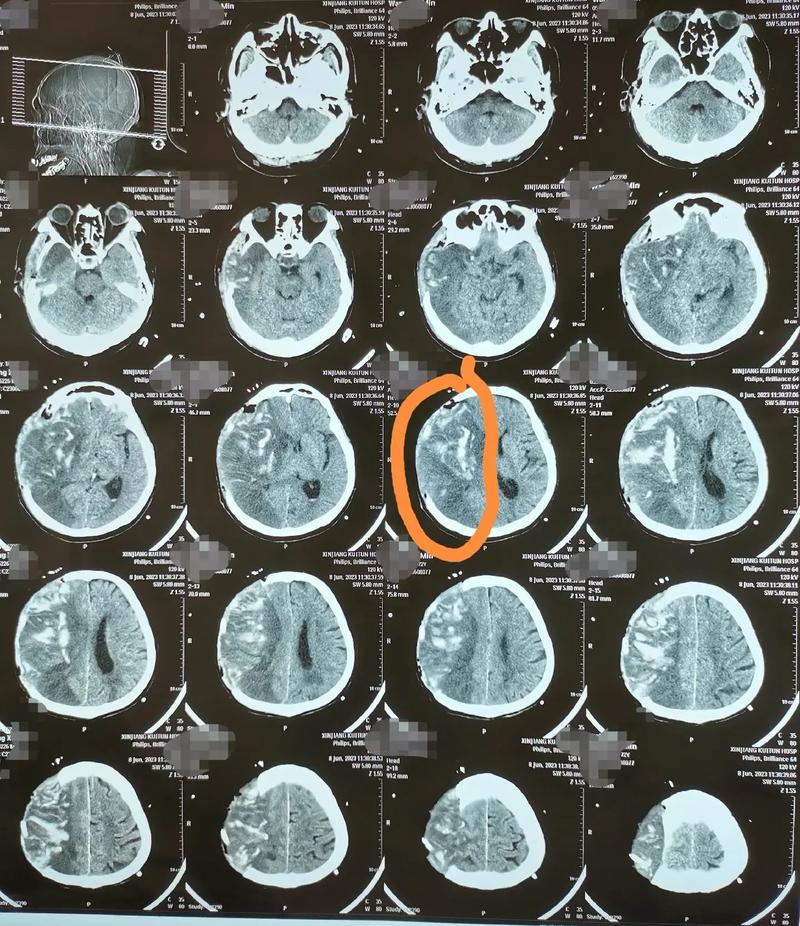

“医生,明明放了支架,为什么脑梗还是复发了?”这是在神经内科及康复科门诊中,我们医生经常听到患者和家属充满困惑与焦虑的提问,脑梗死后放置支架(无论是颈动脉支架还是颅内动脉支架),是为了解决血管严重狭窄或闭塞问题,恢复脑部血流,是现代医学中一项重要的治疗手段,确实有部分患者在支架手术后,短期内或远期仍会发生新的脑梗事件。

这种“支架术后再发脑梗”的情况,不仅让患者和家属感到心灰意冷,更对后续的治疗和康复带来了巨大挑战,作为您的健康康复医生,我将结合临床经验与前沿研究,为您深度剖析这一现象背后的原因,并提供一套科学、系统、可操作的预防与康复方案,帮助您真正走出“梗”局,重获健康。

许多患者错误地认为,支架植入后就万事大吉,血管“打通”了,病就“根除”了,支架只是解决了局部的“交通堵塞”问题,但导致脑梗发生的“土壤”和环境并未完全改变,我们可以将支架术后再发脑梗的原因归结为以下五大核心元凶: